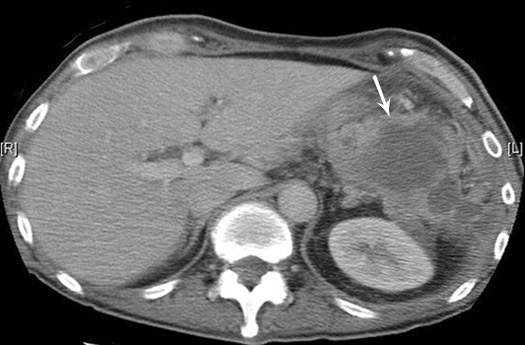

Renal abscess

• 40 year old man with fever and diarrhea for two weeks. He has infected urine.

• IVP shows functioning right kidney (black arrowhead).

• No function in the left kidney.

• Air pockets seen in the left flank (white arrowheads).

CT shows a large mass in the left renal area with multiple air pockets and absence of functioning renal parenchyma.